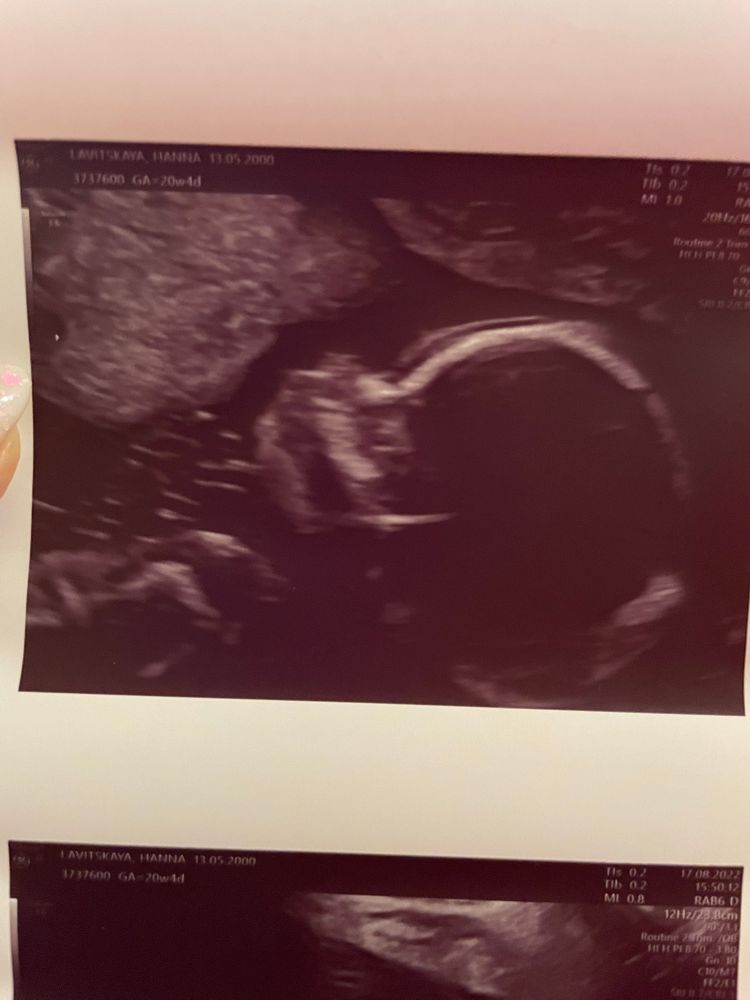

С малышкой все хорошо, на этом УЗИ спокойно лежала, дала себя рассмотреть. Под конец доктор шутила, что ребёнок решил заняться стретчингом, стала потягиваться. Весит +/- 330гр. Я очень рада.